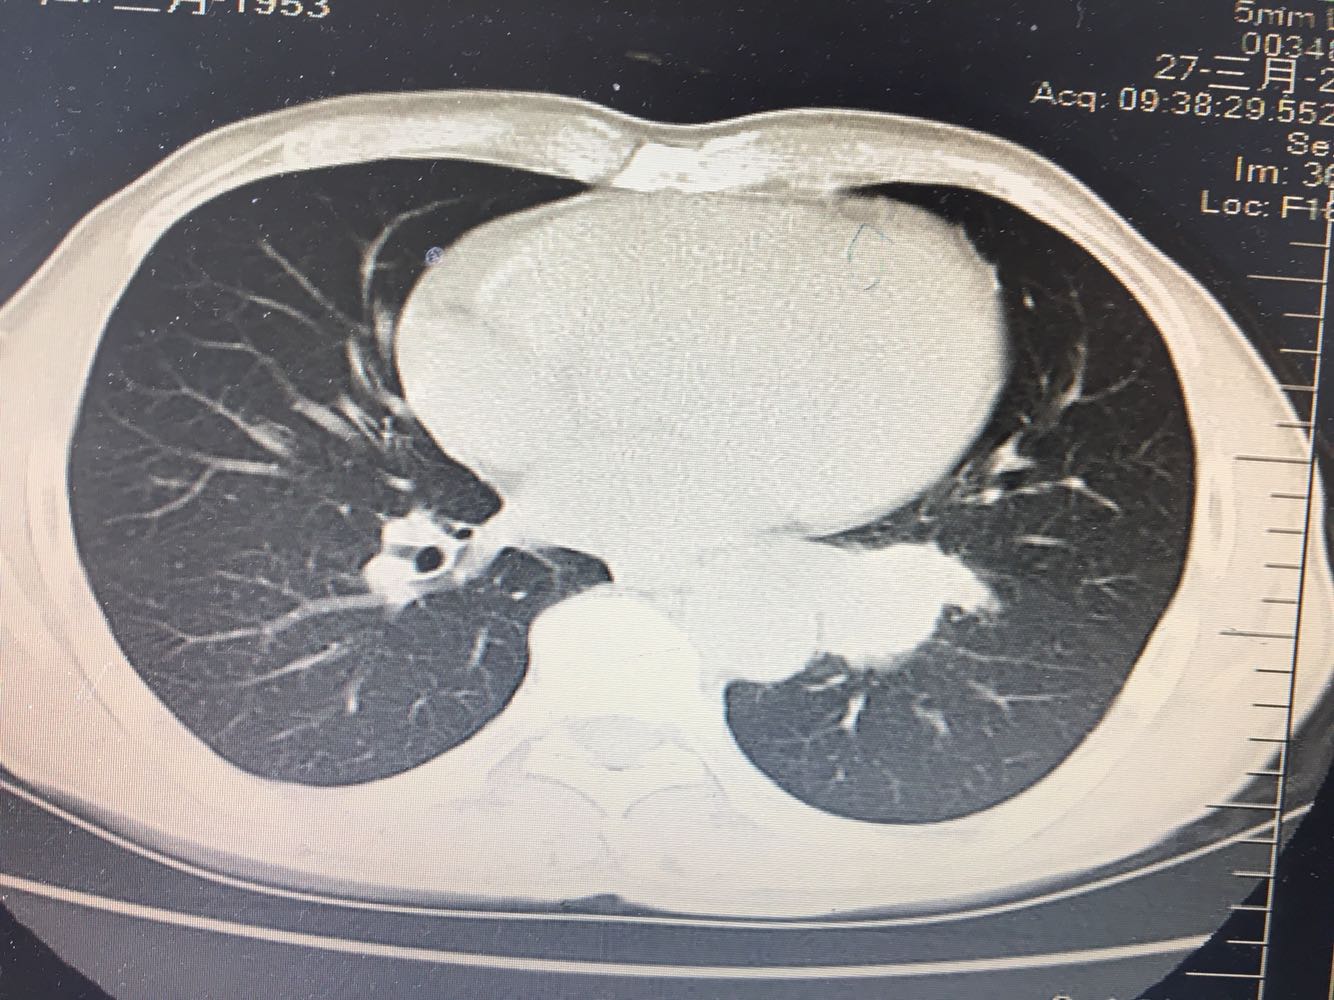

左肺下叶鳞癌

男,63岁,咳嗽1个月入院,患者自述1个月前无诱因咳嗽,阵发性干咳,无痰,时有血丝,无发热,左胸痛,活动后气短,静滴头孢13天无好转,门诊查肺CT后以 肺占位收入我科,病来饮食睡眠可,体重明显下降。既往疝气术后1年,吸烟史30年,每日1包。

左肺癌

左肺中央型肺癌,是否可以手术,还是化疗,放疗,靶向治疗?